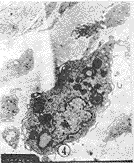

图4 活跃的巨噬细胞,内有许多吞噬颗粒,有微球样均质状物。MEF×4000